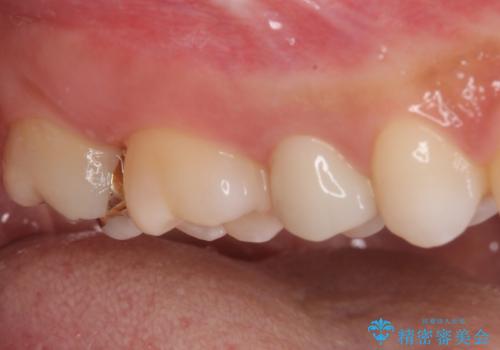

海外転居前にむし歯を治療したい 精密なむし歯治療

- 近々海外へ転居するとのことで、事前に処置をしておくべきむし歯がないか、気にして来院された患者様です。

レントゲン写真などから、速やかに処置を行うべき歯が2歯あったため、それぞれセラミックインレーとPGAインレー(ゴールドインレー)にて修復治療を行うこととしました。

どちらの歯も痛みなどの症状はなく、治療後も異常所見なく経過をたどっています。

上顎大臼歯は向かい合った人から見えることはほとんどないため、切削量が少なく、適合の良いゴールドインレーが大変おすすめとなります。